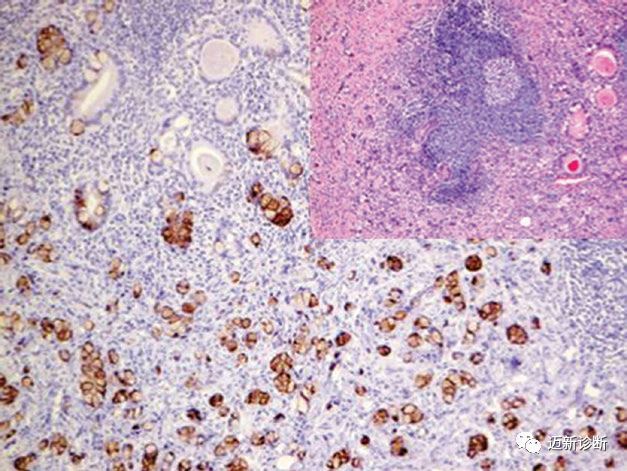

图片

图3. 腹水中的卵巢癌细胞,免疫组化Claudin-4阳性。